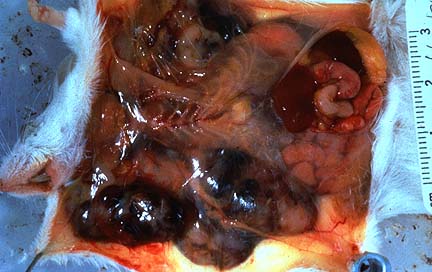

Gross Pathology: Postmortem findings included extensive oral erosions and a generalized pneumonia consisting of multifocal consolidation most prominent in the ventral areas.

Gross Pathology: Two sheep were necropsied. There was abundant clear fluid in thoracic and abdominal cavities and marked perirenal edema. Kidneys were swollen, pale, and had pinpoint hemorrhages over the capsular surface.

There is a diffuse degeneration and attenuation of the epithelium of proximal and distal tubules. There are many intratubular proteinaceous casts and some necrotic cell debris in collecting ducts. There are a few foci of early tubular regeneration.

Mortalities were probably associated with cardiac arrest due to electrolyte imbalances, including hyperkalemia, resulting from acute renal failure. There are no previous documented reports of Amaranthus hybridus causing renal failure in sheep.

Reports of toxicity following the grazing of the closely related species Amaranthus retroflexus (redroot) have been associated with severe perirenal edema and nephrosis in cattle and pigs. The nephrotoxic principle in Amaranthus has not yet been described. Phenolic compounds which have been identified in the leaves of Amaranthus retroflexus may be involved in the syndrome. The abundance of Amaranthus hybridus on otherwise bare ground had resulted from its rapid germination after 7 months drought, then a good fall of rain. Oak shrubs and trees (Quercus spp.) cause a similar condition in ruminants and horses; in this case the toxic principle has been shown to be tannins.

Conference Note: Redroot pigweed (Amaranthus retroflexus) has been reported as a cause of perirenal edema and acute renal failure in swine, cattle, and, less frequently, horses. Grossly, Amaranthus intoxication produces perirenal edema and occasionally edema of the intestine, mesentery, and ventral abdominal wall. Ascites and hydrothorax may also develop. The kidneys are pale, but usually not enlarged. Histologically, there is degeneration and necrosis of tubular epithelium. Glomerular hypercellularity and necrosis may also be present; in this case, some of those attending the conference noted multifocal necrosis of cells within glomerular tufts. Another finding in this case is the presence of hyaline droplets, eosinophilic homogeneous globules of protein, within the cytoplasm of tubular epithelial cells. Hyaline droplets are lysosomes distended by protein that is being degraded for return to the circulation as amino acids. The presence of hyaline droplets indicates that the process of protein resorption by proximal tubules is saturated.